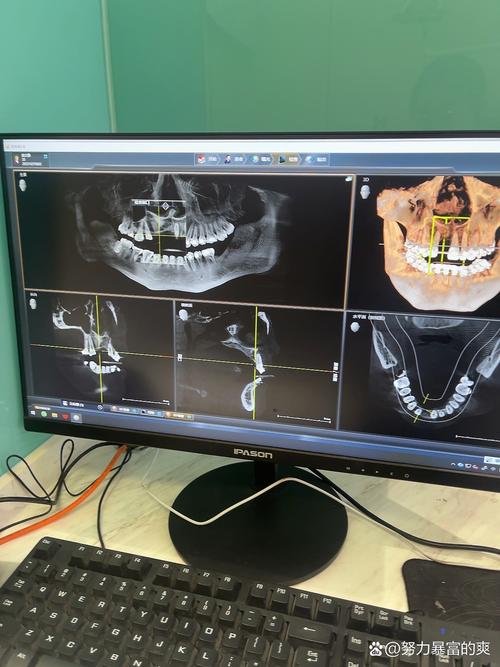

术前需通过锥形束CT(CBCT)或口内扫描仪获取患者颌骨的精准影像数据,CBCT可生成三维立体图像,清晰显示牙槽骨的厚度、密度、高度,以及重要的解剖结构如下牙槽神经管、上颌窦、颏孔等,这些数据导入专用导航软件后,系统会自动重建患者颌骨的三维数字模型,为后续手术规划提供“解剖地图”。

- 影像采集:拍摄CBCT(层厚≤0.3mm)及口内扫描数据,获取颌骨与牙列的精准三维信息。

- 数据重建:将影像数据导入导航软件,生成颌骨三维模型,标注重要解剖结构(神经管、上颌窦等)。

- 虚拟种植:医生在软件中模拟种植体植入,调整位置、角度、深度,生成最优手术方案,并保存为导航文件。